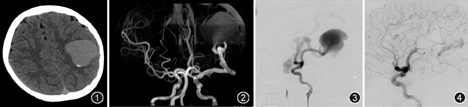

影像表现:CT显示左侧外侧裂池及左侧额顶颞部多发迂曲、囊状扩张的高密度血管影,管壁见多发斑片状高密度钙化(图1);MRI及MRA显示左侧大脑中动脉扩张,左侧额顶颞部见迂曲、增粗的引流静脉,二者间见瘤样扩张的血管,上矢状窦及左侧横窦稍扩张(图2)。

介入手术:造影见左侧大脑中动脉供血的脑动静脉瘘,有静脉湖样结构(图3),向侧裂及矢状窦引流。超选择左侧大脑中动脉,将4 mm×20 mm Scepter球囊置入瘘口近心端,复查造影见血流明显降低,先通过球囊导管及栓塞导管将1个Cosmos 4 mm×12 cm及1个Axium 4 mm×12 cm弹簧圈相互缠绕置入瘘口,然后依次再放入3个Cosmos 4 mm×12 cm弹簧圈、1个Cosmos 3 mm×7 cm弹簧圈,然后注入Onyx胶2.5 ml,复查造影栓塞满意,瘘口闭塞,原静脉湖样结构消失(图4)。